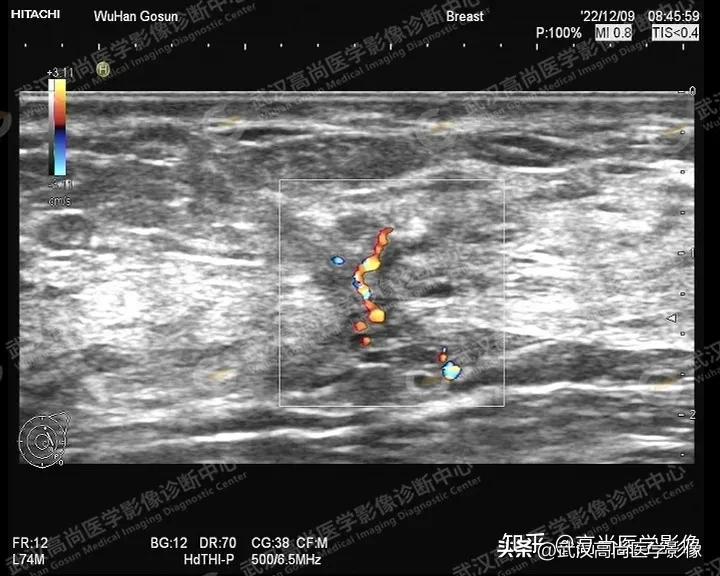

图一、图二、图三:右侧乳腺10点钟方向实性肿块,形态不规则,轮廓不规整,成角,大小约33x24x28mm,内部回声不均匀,内部见散在点状钙化,内血流信号丰富。